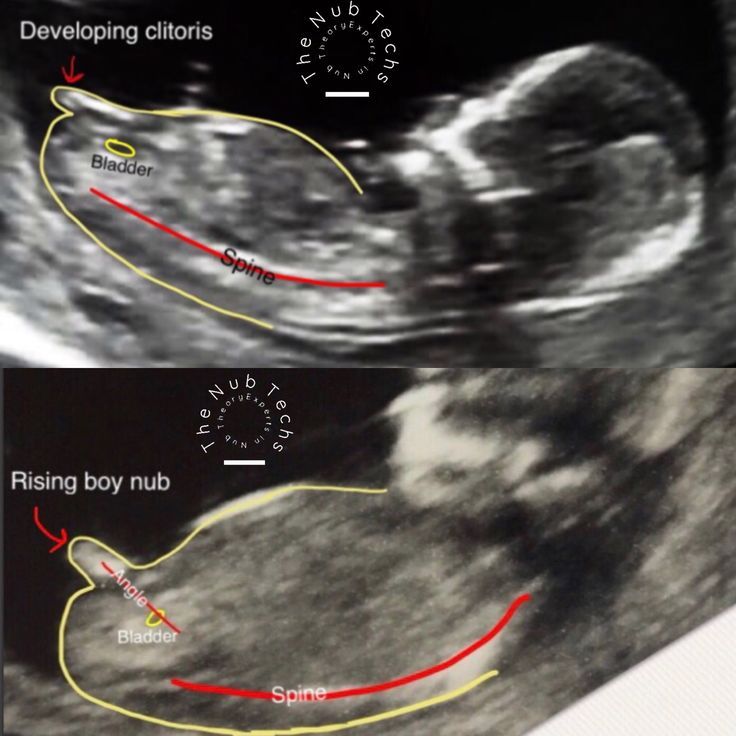

Я за мальчика)) если то, что на фото бугорок, а не пуповина или тень от ножки.

смотрят наклон полового бугорка, у девочек и у мальчиков до 14 недель одинаковые половые органы на вид, но по разному направлены относительно позвоночника)

Olya, по наклону полового бугорка. У мальчиков он более приподнят, чем у девочек, но внешне выглядят одинаково и те, и другие)) Поэтому нужен хороший специалист и аппарат УЗИ, чтобы так рано сказали точно.